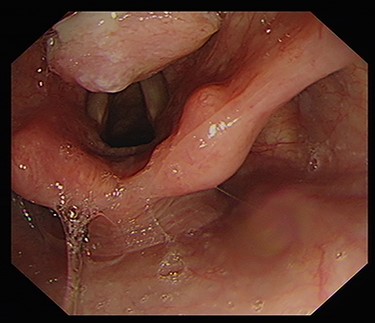

A laryngeal abnormality was noted, and he was referred to ENT for further assessment (Fig. 1). Flexible nasendoscopy showed a lesion on the laryngeal surface of the epiglottis in the midline. Vocal cords were not affected, although the lesion was extending close to the anterior commissure. An 18 × 14-mm lesion was found on magnetic resonance imaging (MRI) at the right paracentral supraglottic region, crossing the midline with possible involvement of the base of epiglottis (Fig. 2). There was no destruction of the thyroid cartilage or hyoid bone, and no involvement of the para-epiglottic space or glottis. There were no pathological cervical lymph nodes. Further CT scanning of the neck and chest confirmed the above, with no lung metastases identified (Figs 3 and 4).

endoscopic image demonstrating ulcerative growth on the laryngeal surface of the epiglottis.